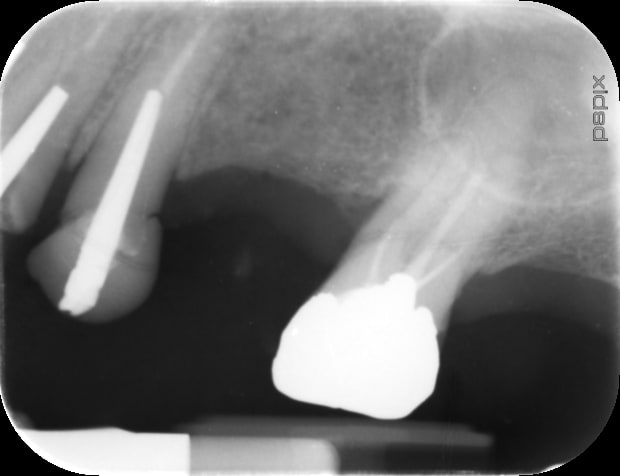

Là il s'agit d'une 27 d'une connaissance, traitée il y a longtemps par un dentiste voisin maintenant quasi à la retraite.

J'en suis à moins d'1/5 de la LT (vu la radio) de la racine MV.

Un parodontite apicale (chronique) sur la racine mesiale, avec une desmodontite.

Rien de spécial en somme, si ce n'est que mon reciproc tourne dans le vide contre ce qui semble être du materiau d'obturation.

Voilà j'ai revu jeudi le patient, pour continuer la reprise de traitement.

J'ai mis en application vos conseils, et j'ai pu progresser. Mais.. je suis encore loin des apex.

- la racine MV : en passant le réciproc (que j'ai emprunté à mon collaborateur) j'ai pu progresser dans le canal sur quelques mm (j'étais étonné qu'à chaque rotation, je m'enfonçais d'un demi mm).

- la racine DV, j'étais bien sur une butée (Cf dent2660 ci dessus), et j'ai réussi à retrouver le chemin vers le canal en direction de l'apex.

- la racine P j'aimerai progresser de 2-3mm encore

Sur ces trois racines, mon reciproc tourne dans le vide et ne progresse plus. J'ai essayé de mettre de l'EDTA en gel (un produit qui s'appelle Canal+ ; j'ai également à disposition de l'EDTA 17% liquide en bouteille, si jamais vous pensez que c'est mieux).

Que préconisez vous pour la suite ?

Ci joint la radios pré et les radios per op. Les radios sont issues du pspix2, qualité pas folle.

Certains me disent que je perds mon temps, mais vu c'est une dent stratégique pour placer le futur stellite, j'aimerai la lui conserver.